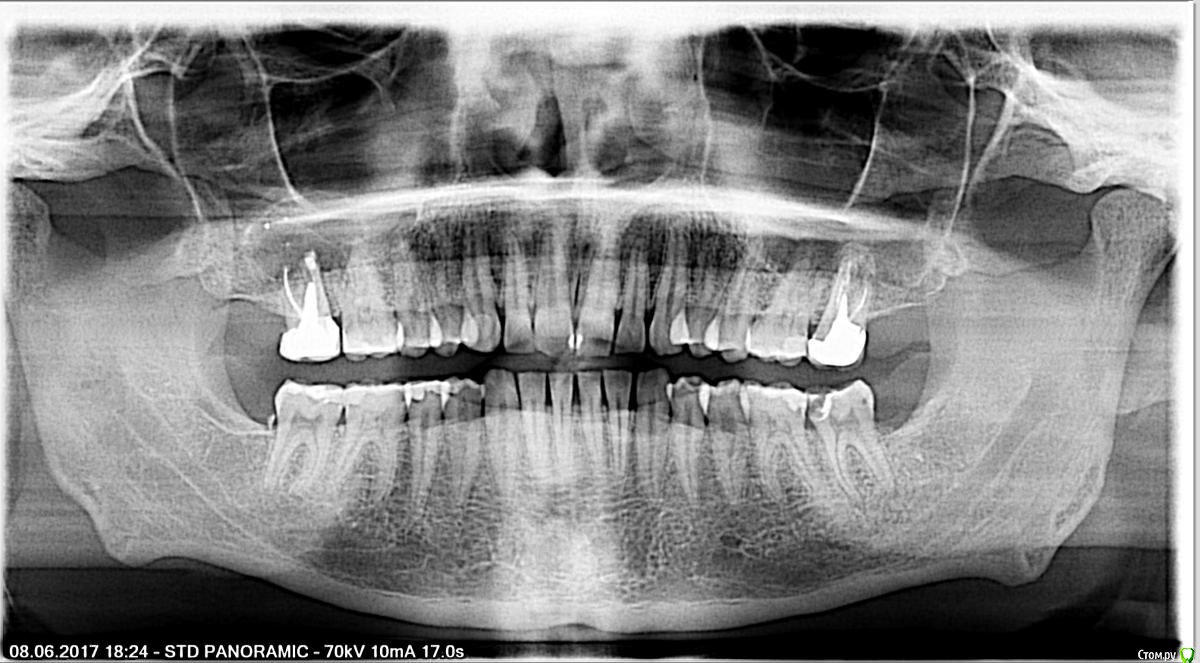

pogoreliy Опубликовано 15 июня, 2017 Автор Поделиться Опубликовано 15 июня, 2017 (изменено) Доброго времени суток. Располагаю мнением врача из клиники, которое многое расставило на места. Тем не менее, хотелось бы чистого взгляда со стороны, не обремененного посторонним видением ситуации. Так же очень прошу изучить панорамный снимок на предмет еще каких-нибудь необъявленных подарков. Дело в том, что на вышеописанном зубе этот самый кариес как раз и не разглядели (с распечатанной бумажки). С тех пор уверенности, что завтра-послезавтра ещё какой-нибудь зуб мне вероломно не объявит, что он почти издох от очередного запущенного троянско-кариесного коня, нет никакой. До боли обидно, когда все кариесы на свете выполоскал-вычистил, а он возьми да и чуть ли не изнутри зуб начни крошить. Изменено 15 июня, 2017 пользователем pogoreliy Ссылка на комментарий

DmitrySH Опубликовано 15 июня, 2017 Поделиться Опубликовано 15 июня, 2017 На снимке связка зуба расширена, что свидетельствует о наличии воспаления. Убирайте нерв. Еще надо обратить внимание на верхние седьмые. На снимке все неоднозначно. Лучше сделать КТ Ссылка на комментарий